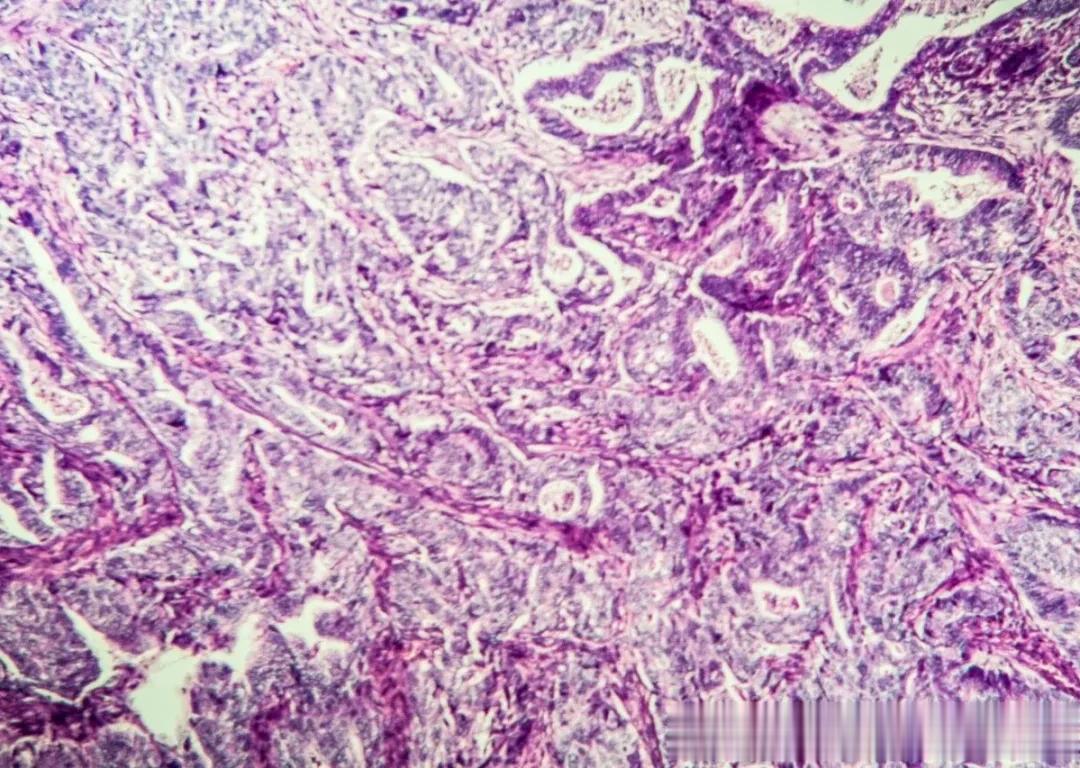

最终胃镜病理确诊:低分化腺癌,部分为印戒细胞癌,HP(-)。

术后病理诊断:低分化腺癌,大部分为印戒细胞癌;淋巴结转移情况:取了35枚淋巴结,其中27枚有转移。